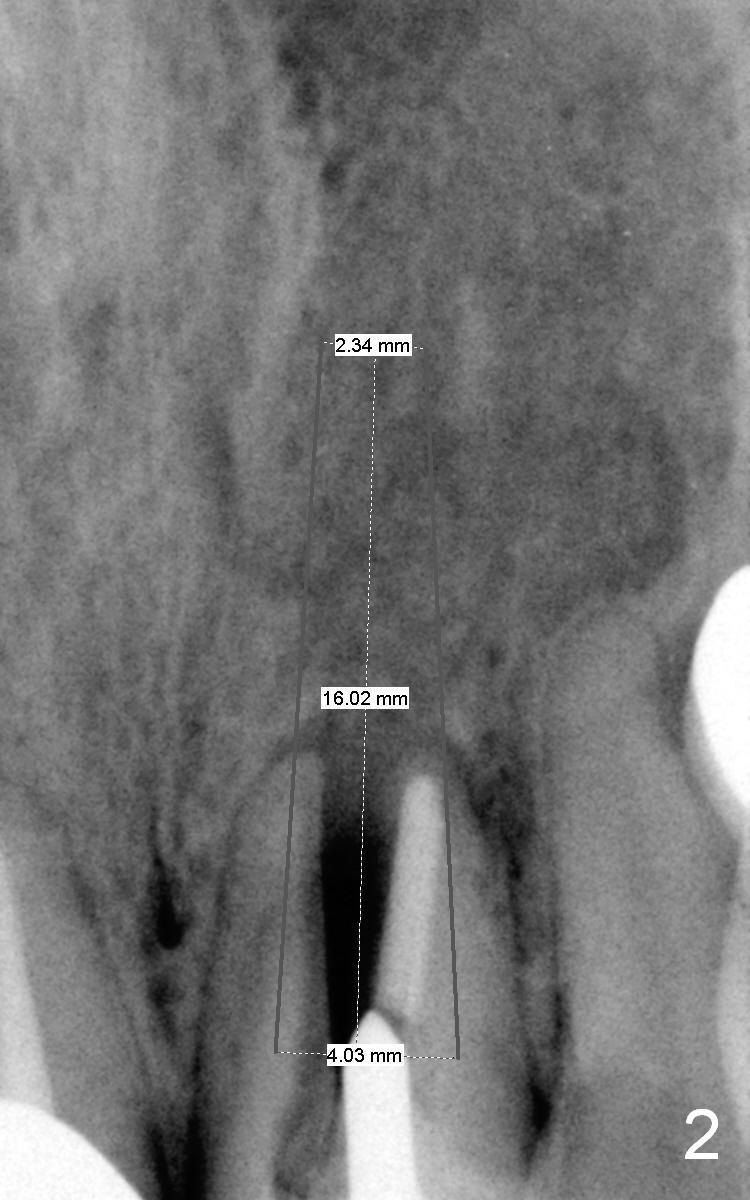

A 64-year-old woman (XP) has multiple restoration, requesting implant replacement for the loose upper left central incisor (Fig.1).  It is asymptomatic, although there is labial swelling with purulent discharge from the labial gingival sulcus.  The labial plate must have been absent.  After granulation tissue removal and socket treatment with no antibiotic, place a 4x16 mm implant in a correct position (Fig.2).  Place Osteogen tape against the labial defect and then bone graft with a small piece of gauze in the implant well.  Since the lady is small in stature with possible osteoporosis and X-ray is particularly dark (Fig.2 (Fig.1 has been lightened in brightness)), use low voltage when taking new X-ray.  Take preop photos to show labial swelling and purulent discharge from the labial gingival sulcus.